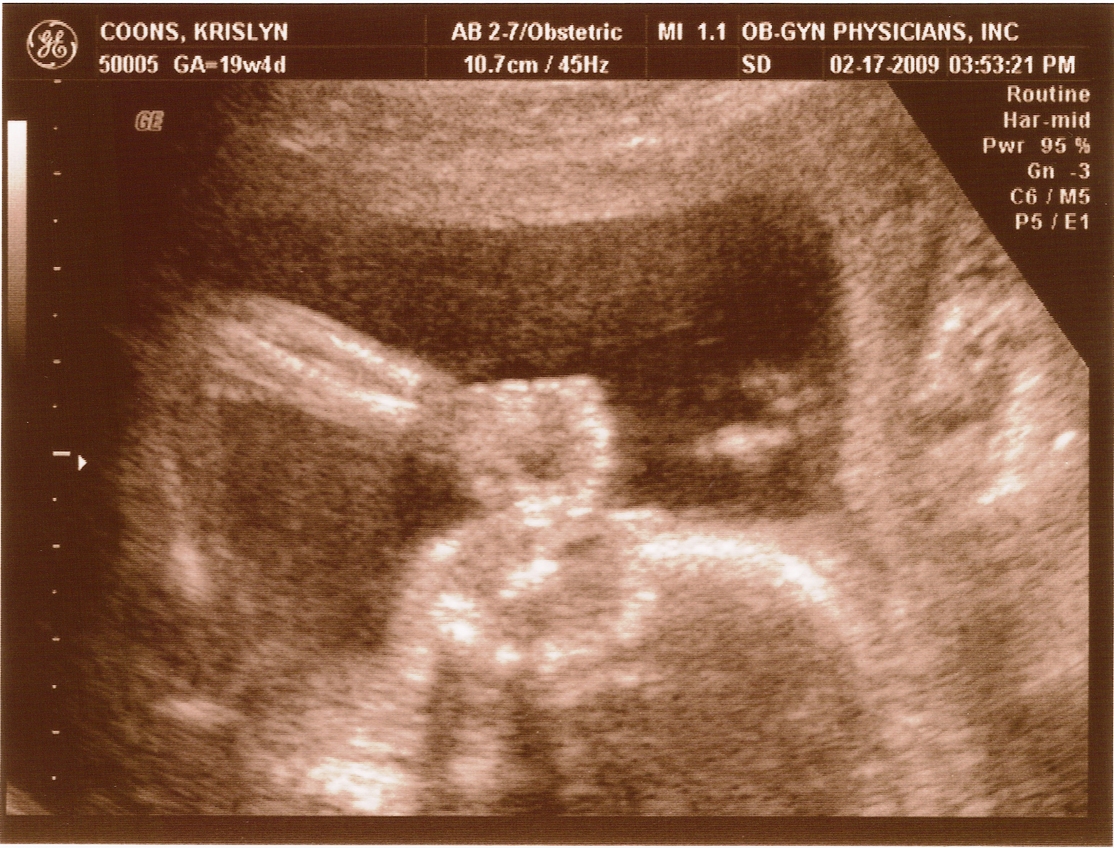

20 weeks -

Arm & Head

2.17.2009

First ultrasound! The baby measures right on target and appears to be developing normally. All looked and sounded great. Krislyn is finally gaining some baby weight too!